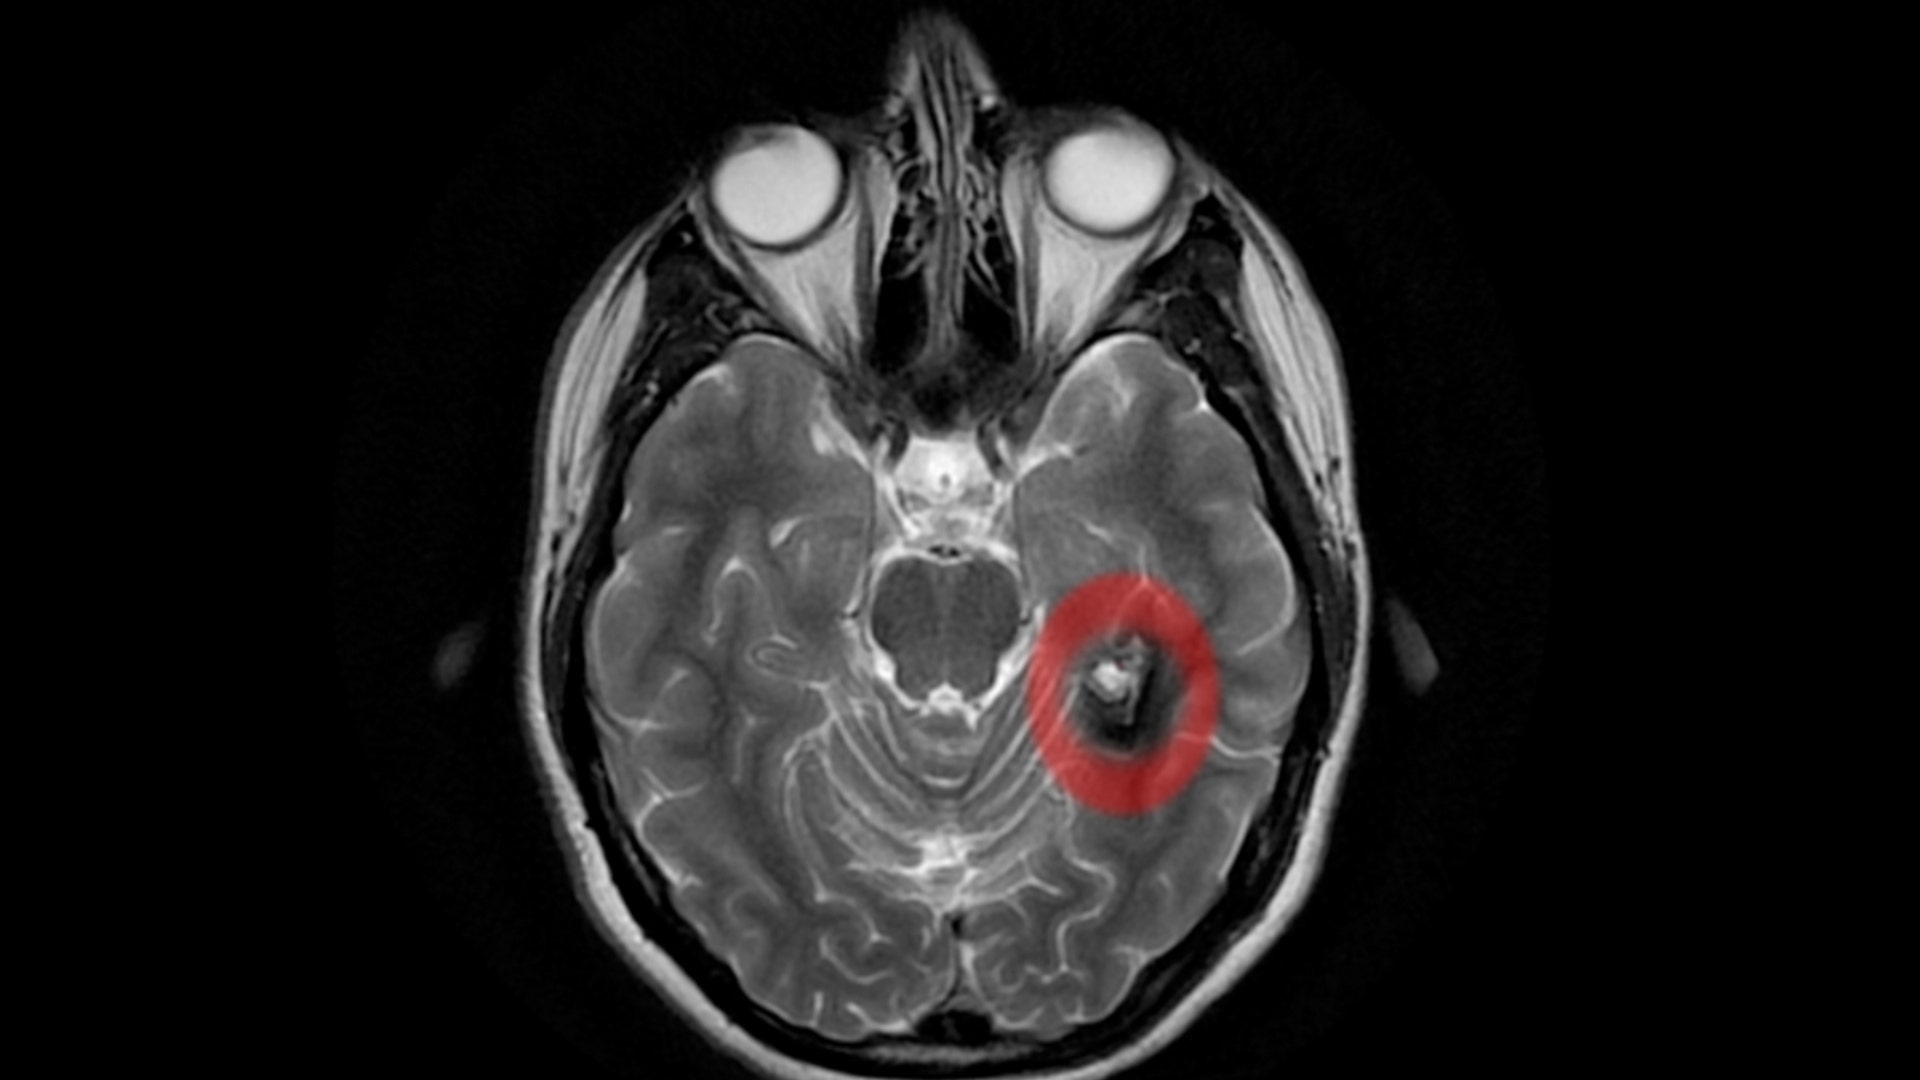

In December 2006, Silva, of North Bergen, N.J., was diagnosed with a cavernous malformation - or a tangle of blood vessels, located on the part of left temporal lobe of her brain where the memory and language are. Since a cavernous malformation is really a tangle of blood vessels, Silva's doctor said the concern is bleeding. "Cavernous malformations are considered to be low pressure, so though they can bleed, they tend to bleed in small increments," said Dr. Steven Karceski, a neurologist at Columbia-Presbyterian Medical Center in New York who has treated Silva. "Whereas something like an aneurysm - while it does bleed, it can tend to bleed in a more serious way."read more![Back View of Alison's MRI]()

Karceski said doctors think malformations like Silva's are formed around birth or very early in a person's life, and it only becomes a problem when a problem is recognized. "In Alison's case, it was the headaches, and some of the things that she was experiencing that brought her to a doctor, which led to the diagnosis," Karceski said." She was always, even before this happened, a very creative person, and shes aid that what occurred after the bleed was that her creativity took a different direction, and she felt that her creativity became richer and deeper."read more